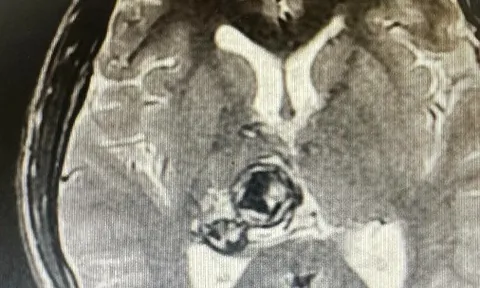

Nam sinh viên 20 tuổi phát hiện khối u não sau khi thấy đau đầu, chóng mặt

Nam sinh viên 20 tuổi thường xuyên có hiện tượng đau đầu, chóng mặt. Đi khám được xác định u não nhưng bị từ chối can thiệp do u nằm sâu trong não.